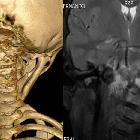

Plain radiograph and CT

- intramedullary or subcortical lucent foci may be the earliest manifestation

- this progresses to profound osteolysis with resorption of affected bone and lack of compensatory osteoblastic activity or periosteal reaction